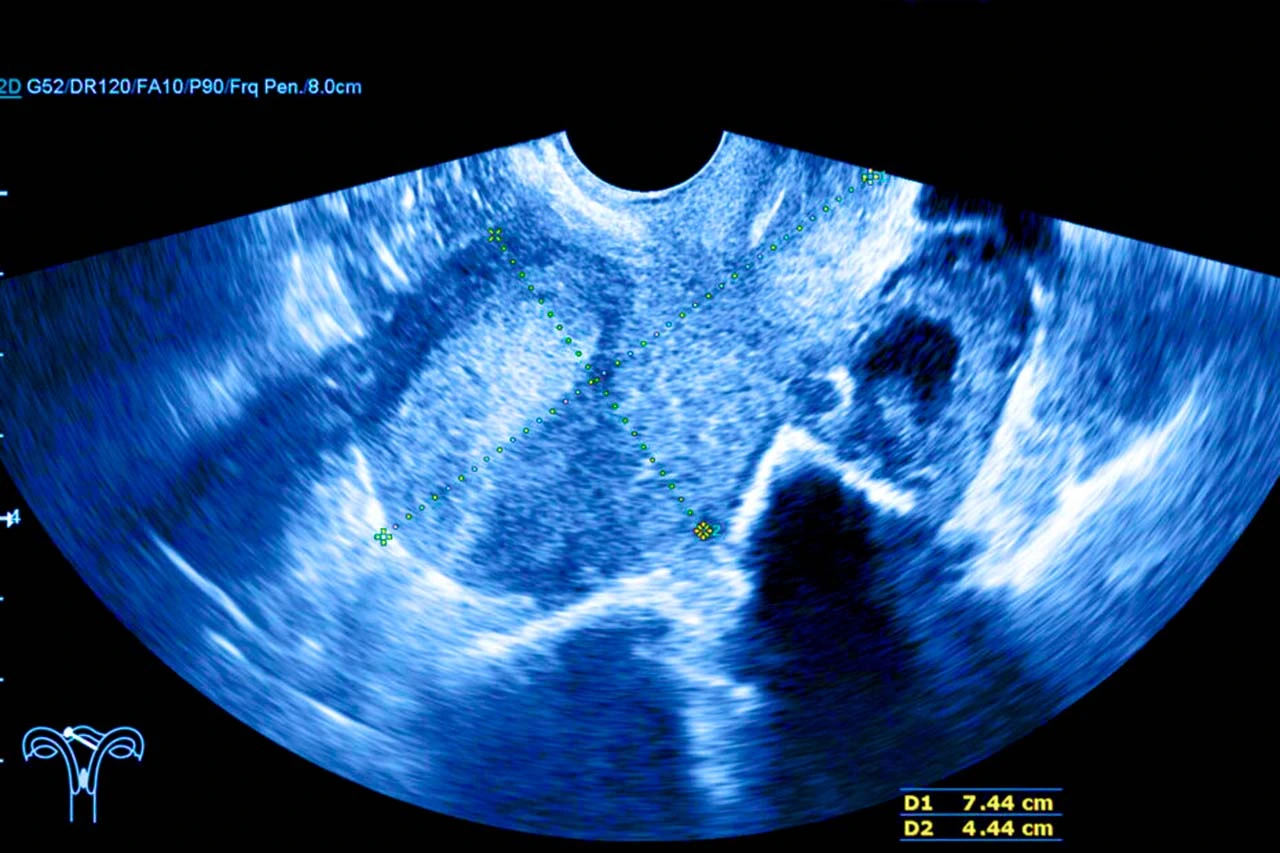

El diagnóstico inicia con una revisión clínica detallada y estudios complementarios como la ecografía transvaginal o pélvica, resonancia magnética, tomografía computarizada, colonoscopía o rectosigmoidoscopia, biopsia con aguja si hay sospecha de que sea un proceso infeccioso o inflamatorio crónico; así como manometría anorrectal.

Imagen de un ultrasonido transvaginal como método diagnóstico para detectar una fístula rectovaginal.